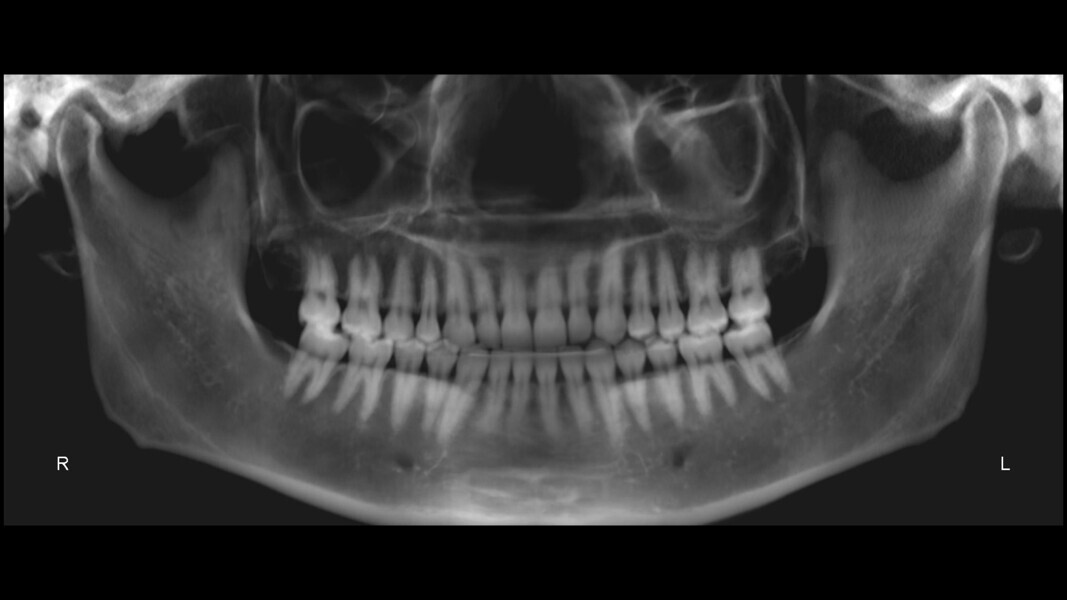

The panoramic radiograph confirmed the presence of all four third molar germs. Notably, there was advanced root resorption in the maxillary arch, although the overall periodontal health appeared good (Fig. 3). The cephalometric analysis showed a Class II skeletal pattern, a vertical growth tendency and posterior mandibular rotation. The maxillary and mandibular incisors were found to be slightly proclined (Fig. 4).